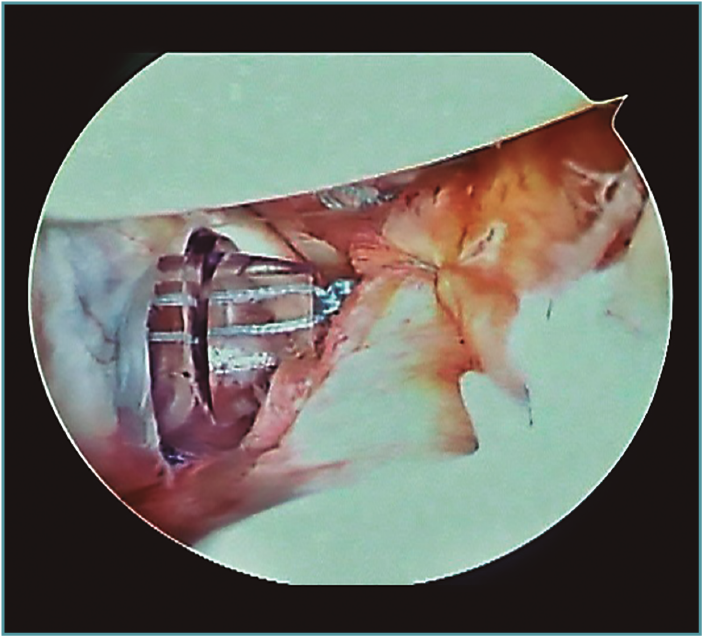

Al realizar la anamnesis, prestamos especial atención a estos síntomas ya que estos episodios repetidos de subluxaciones o microinestabilidad pueden conllevar a lesiones muy complejas e irreparables de la cápsula o, sobre todo, en el cartílago glenoideo (Figura 2).

Figura 2. Visión desde portal posterior del hombro derecho. Se observa una lesión intrasustancia de la cápsula anterior.

Las inestabilidades de hombro que se manifiestan con dolor o subluxaciones son tan incapacitantes como las luxaciones propiamente dichas y en la gran mayoría de los casos requieren resolución quirúrgica(10,11). Hemos visto en varias ocasiones jugadores con cuadros de subluxaciones o microinestabilidad en situaciones de contacto que modifican su técnica de tackle para disminuir la incidencia de estos episodios y de esta forma continuar jugando. Lamentablemente, además de una indefectible disminución de su rendimiento deportivo, estos jugadores a la hora de operarse presentan lesiones capsulares de difícil solución y lesiones condrales precoces.